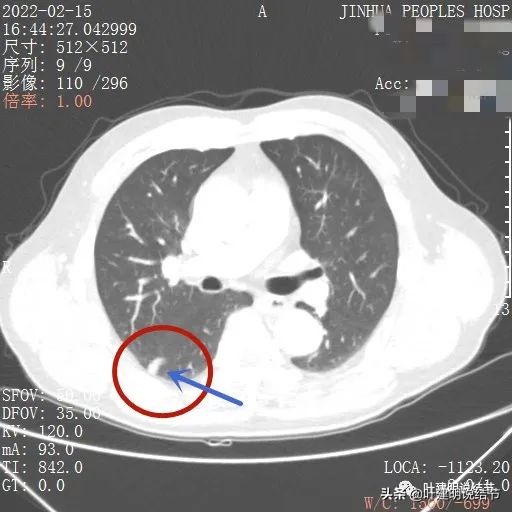

病灶边缘欠平整

叶间裂受到牵拉(蓝色箭头)

也示叶间裂牵拉